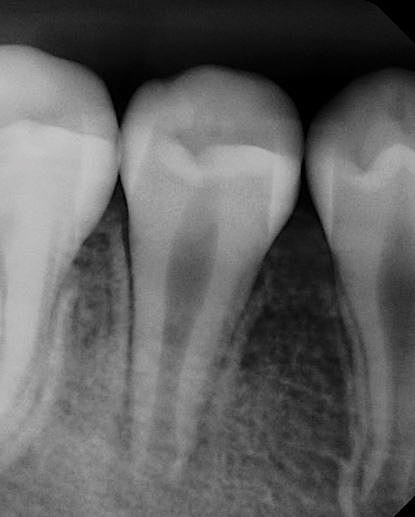

After the canal preparation is completed, it is irrigated with 17% EDTA and dried. Calcium hydroxide is then placed to serve as an antimicrobial medication between treatments (Figure 1).18,19 The canal access is temporized with a sterile cotton pellet or sponge and a temporary restorative material or glass ionomer. The patient is then asked to return in 1 to 4 weeks for the final treatment appointment.15

(1.) Postoperative radiograph of tooth No. 8 with placement of intracanal calcium hydroxide after first visit for regenerative endodontic treatment.

Figure 1